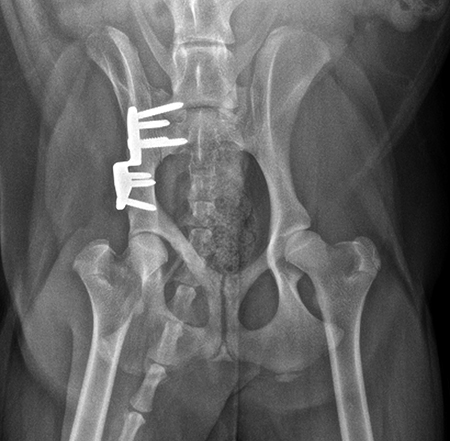

Radiographic examination at 6 months postsurgery revealed stable implants, excellent coxofemoral conformation, and no evidence of osteoarthritis of the right hip. The left acetabulum was mildly shallow and mild subluxation of the femoral head was present at follow-up examination (Fig 6). Early osteophytosis in the region of the left femoral neck was evident. The dog was using the right hind leg normally and was showing no signs of instability or pain of the right hip. Mild instability and pain of the left hip was present on palpation. The dogs left hip was treated with a joint supplement and NSAIDs as needed. Future THR will be performed if clinical signs no longer respond to medical treatment.

Activity was restricted to leash walks for 6 weeks postoperatively. The radiographic examination 1 month after each surgery revealed partial healing of the ilial osteotomy and stable implants. Postoperative radiographs at 6 months after both surgical procedures revealed complete healing of the ilial osteotomies, stable implants, and excellent coxofemoral conformation, with no subluxation of the femerol head. Mild osteoarthritis was observed, however. At both the 4 and 6 month evaluation, the dog was using both hind limbs without any evidence of lameness and was showing no signs of instability or pain of either hip (Fig 10).